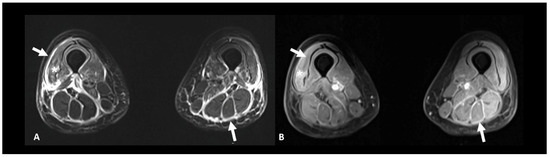

2.6. Ir-Rheumatological and Musculoskeletal Adverse Events

| Myopathy | Serum-specific antibodies, screening for concurrent myocarditis, EMG +/− muscle biopsy | Other causes of myopathy | Muscular T2 hyperintensities | |